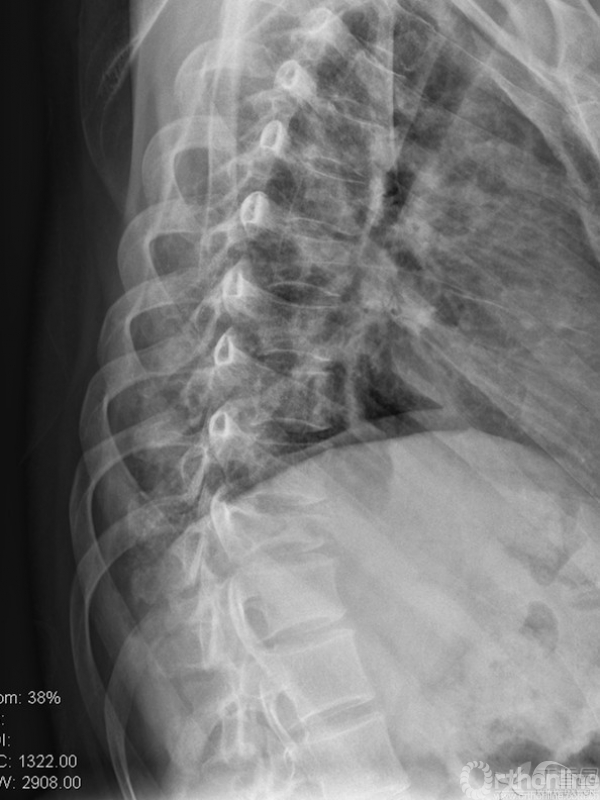

胸椎多椎体病变,如果诊断和治疗?